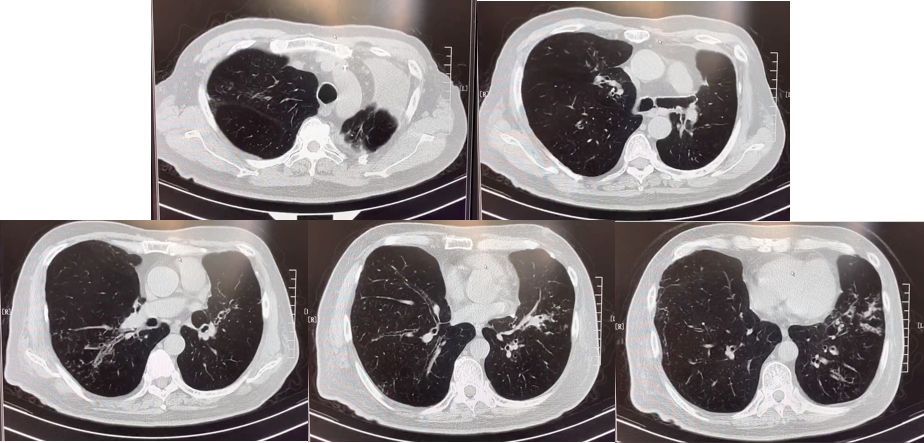

abp在医学是什么意思美例新声病例分享 | 复发活动性变应性支气管肺曲霉病(ABPA)咳嗽患者诊治经验分享_https://www.jmylbn.com_新闻资讯_第7张

2019年5月胸部CT

abp在医学是什么意思美例新声病例分享 | 复发活动性变应性支气管肺曲霉病(ABPA)咳嗽患者诊治经验分享_https://www.jmylbn.com_新闻资讯_第8张

2020年5月胸部CT